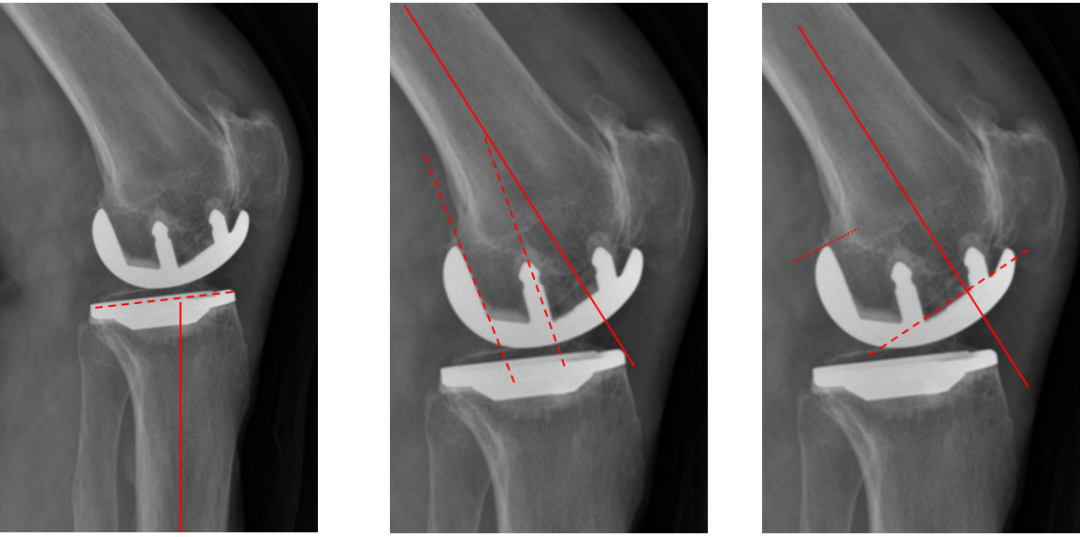

标准股骨假体位置

侧位胫骨与股骨假体位置:胫骨假体后倾7°,前后缘齐平;股骨远端截骨面与股骨长轴垂直,股骨后髁假体后倾15°,完整包容股骨后髁。

胫骨假体后倾角大

侧位胫骨假体位置:胫骨假体后倾11°,前后缘齐平。

胫骨假体前倾

侧位胫骨假体位置:胫骨假体前倾5°,前后缘齐平。

股骨假体后倾不足

侧位股骨假体位置:股骨假体后倾5°,后髁包容不足。